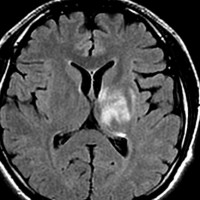

放射線治療13週目

右はガドリニウム増強です。ステロイドとグリセオールの点滴では制御できませんでした。悪性神経膠腫の病名で保険適応があるアバスチン(ベバシズマブ 10mg / kg)の投与を開始しました。